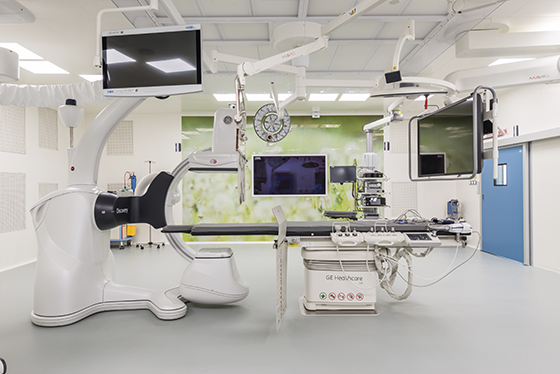

Хирургическое вмешательство

Цель хирургического вмешательства заключается в удалении раковой опухоли и части здоровых тканей во время операции. При раке головы и шеи используются следующие операции:

Исходя из расположения, размеров, вида рака, процесс лечения будет проходить поэтапно с проведением нескольких операций.. При невозможности полного устранения опухоли рекомендуются дополнительные процедуры. Если раковые клетки остаются после оперативного вмешательства, назначают другие виды онкологической помощи (радио-, химиотерапия) в сочетанном или изолированном виде.